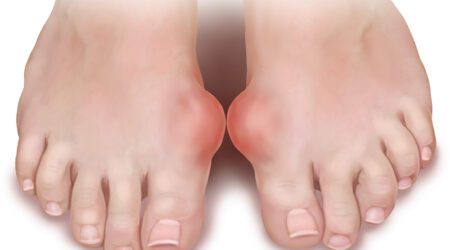

ألقى تقرير صحي جديد الضوء على حالة سلس البول، التي تُعد اضطراباً شائعاً يتمثل في فقدان السيطرة على المثانة والتسرب المستمر للبول، مشدداً على أن فهم الأنواع المختلفة للحالة هو مفتاح تحديد العلاج المناسب. ووفقاً لمصادر طبية، يتضمن العرض الرئيسي لسلس البول تسرب البول قبل الوصول إلى الحمام أو أثناء الأنشطة التي تزيد الضغط داخل…